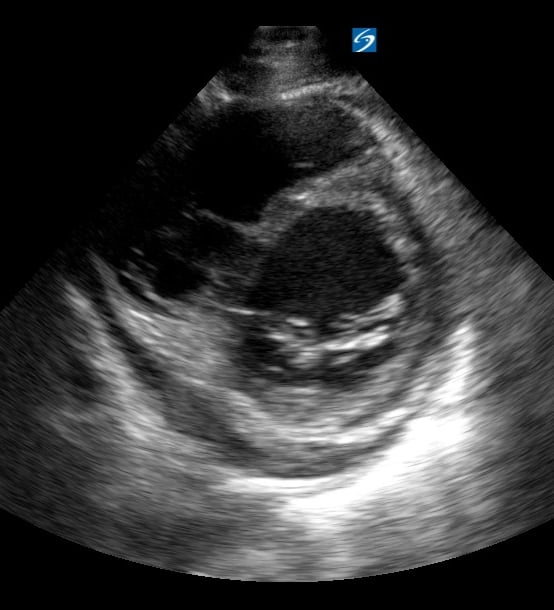

Pericardial effusion in cardiac ultrasound refers to an abnormal accumulation of fluid within the pericardial sac, the double-layered membrane surrounding the heart. This condition can impede the heart’s ability to fill and pump blood effectively, potentially leading to cardiac tamponade, a life-threatening emergency. Early detection through echocardiography is crucial for timely medical intervention and improved patient outcomes.

Utilizing medical ultrasound, healthcare professionals can accurately identify and quantify pericardial effusions, assessing their size, location, and hemodynamic impact. Ultrasound imaging provides real-time visualization of the fluid build-up, enabling precise diagnosis and guiding potential therapeutic procedures such as pericardiocentesis. This non-invasive technique is indispensable for managing cardiac health and preventing severe complications.